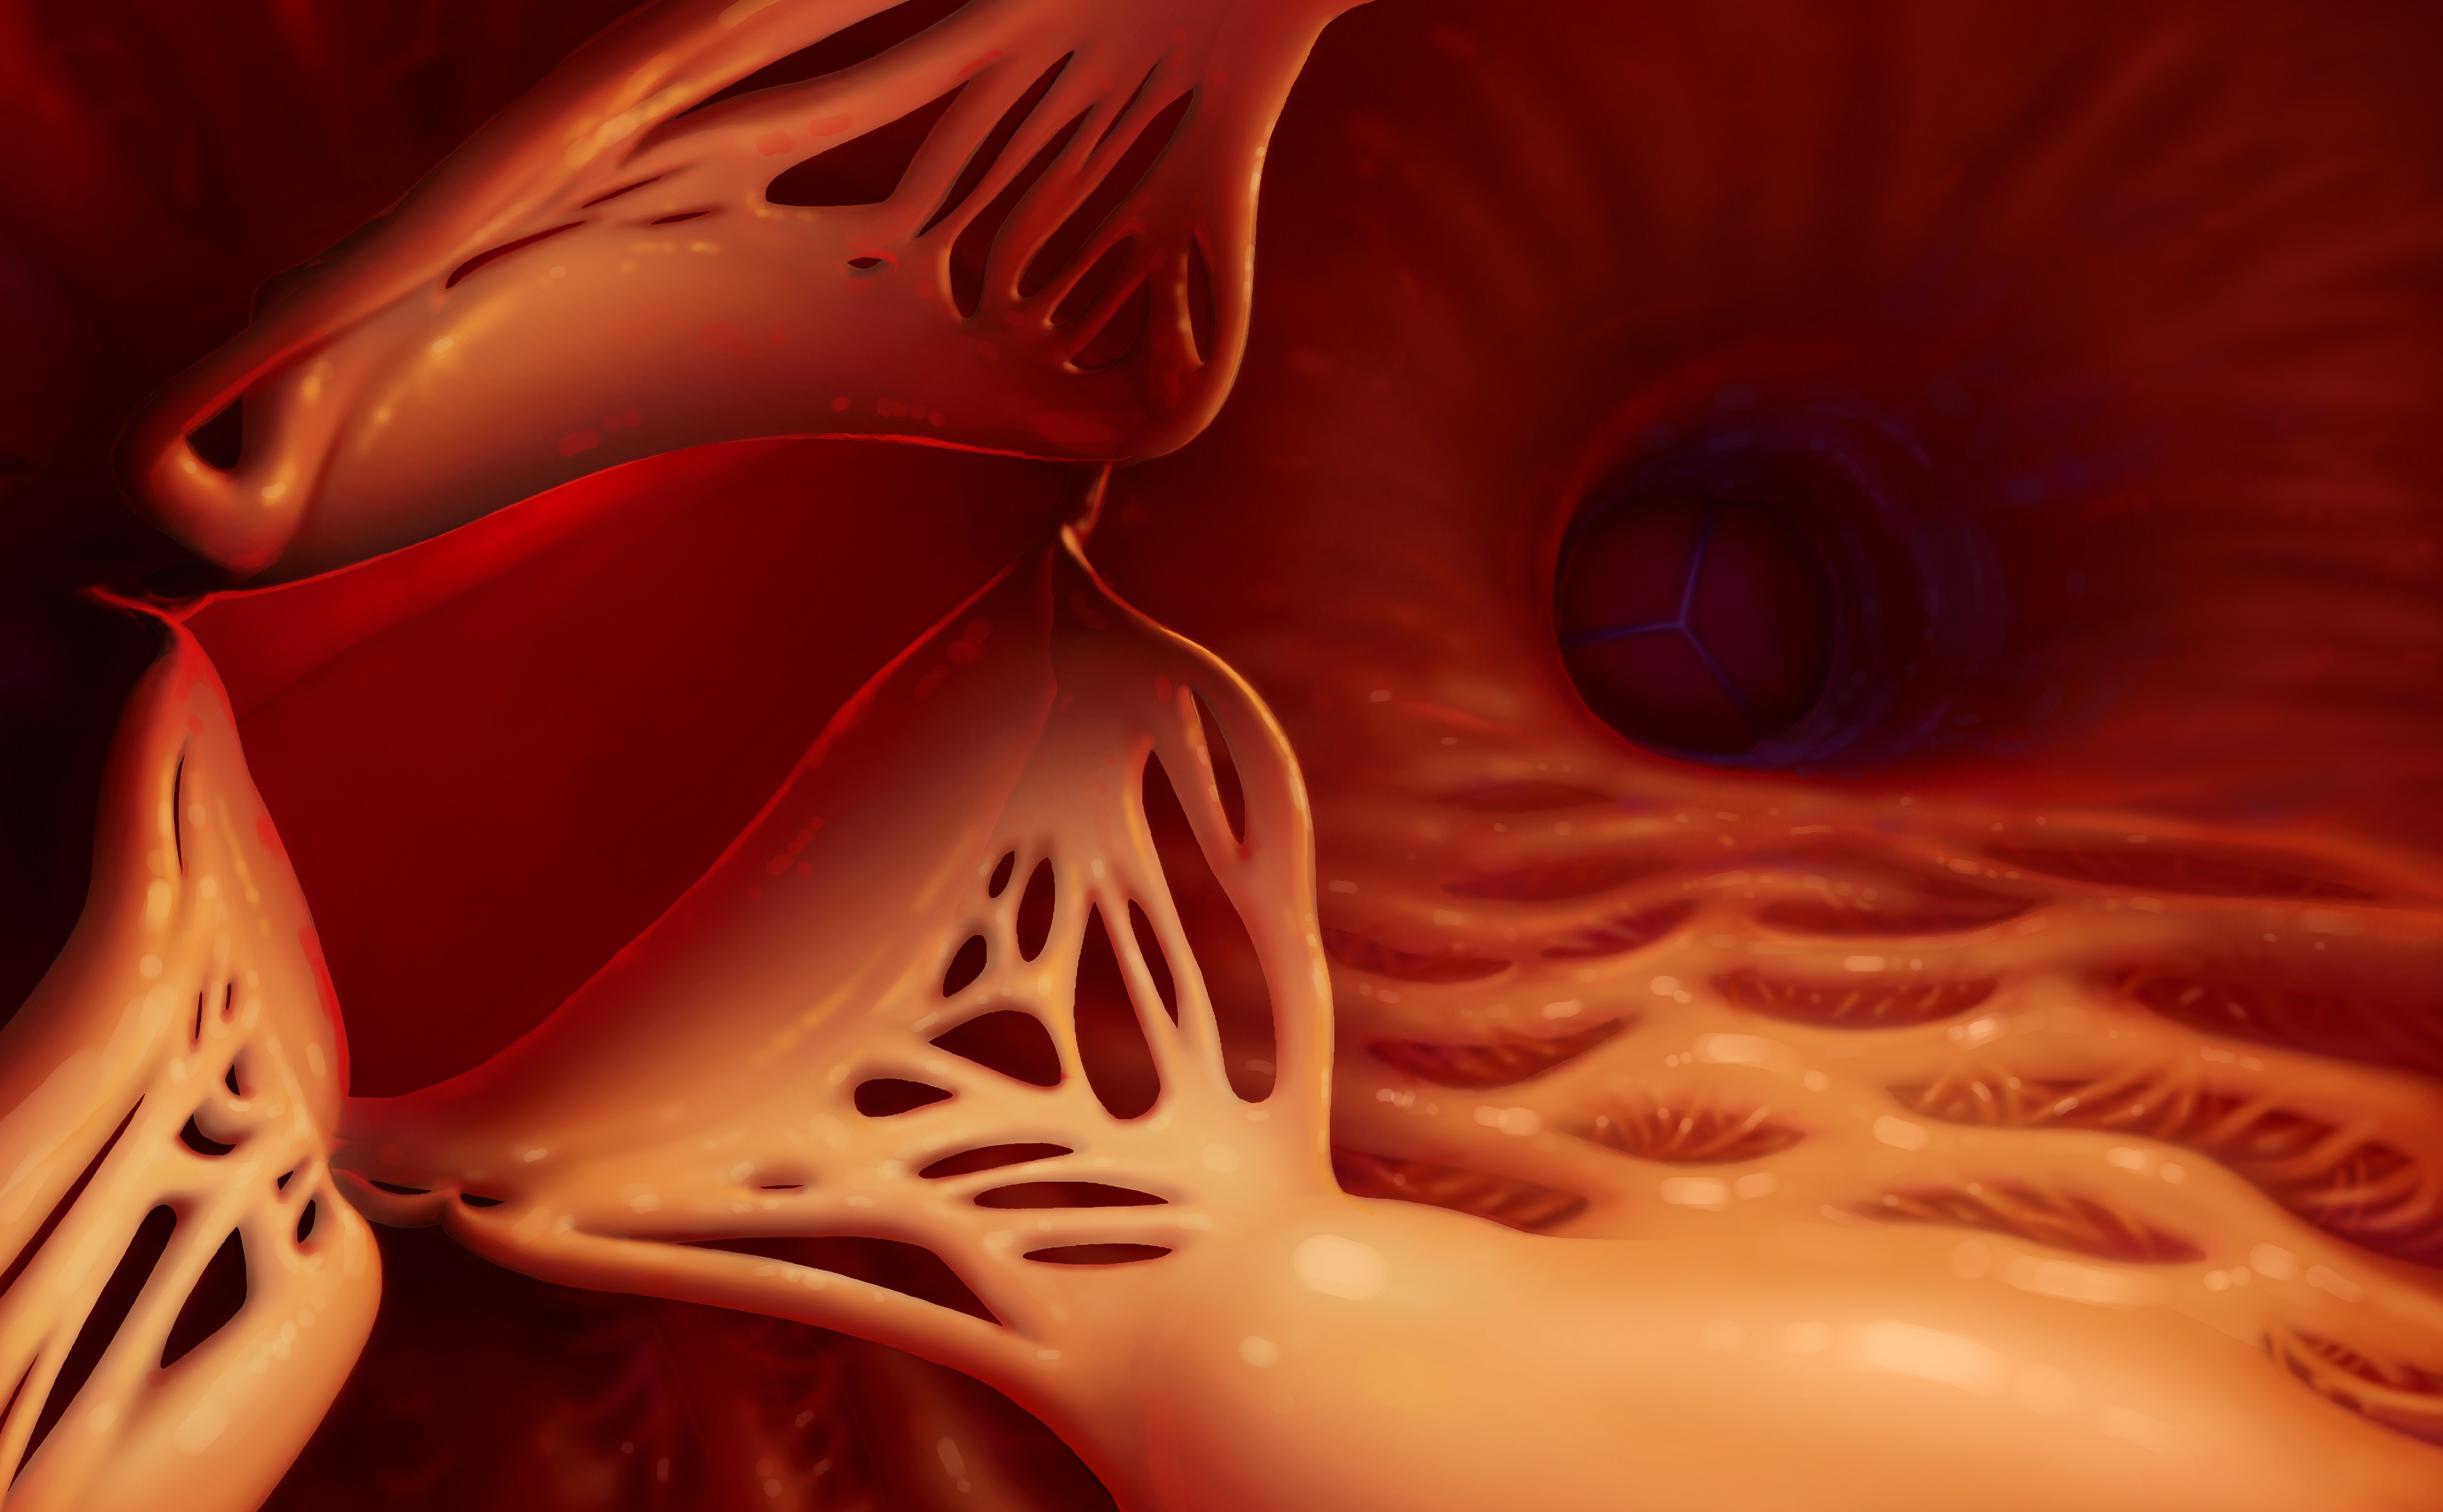

Final concept for the slice view of the heart.

I created a story board of what it would look like to fly through this heart